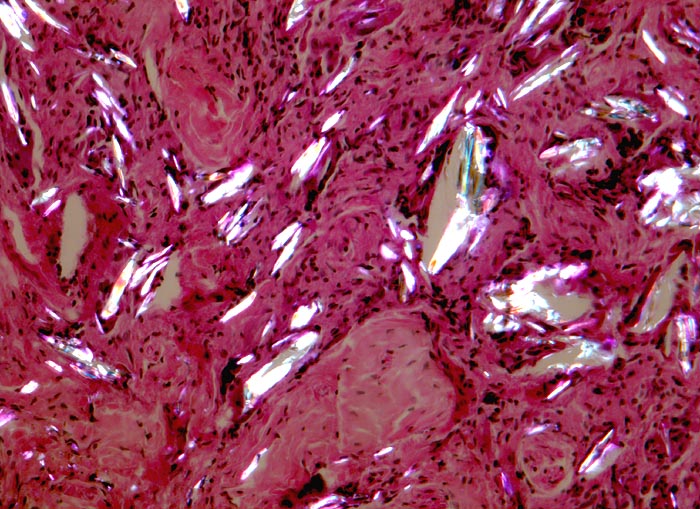

Fremdkörpergranulom

Artefakt / Fremdkörper / Pigment

Weichteile

Doppelbrechung: Entzündlich infiltriertes Bindegewebe mit hell aufleuchtendem doppelbrechendem, kristalloidem Fremdmaterial, welches teilweise von Fremdkörperriesenzellen umgeben oder von Ihnen eingeschlossen ist.

Histologie

160